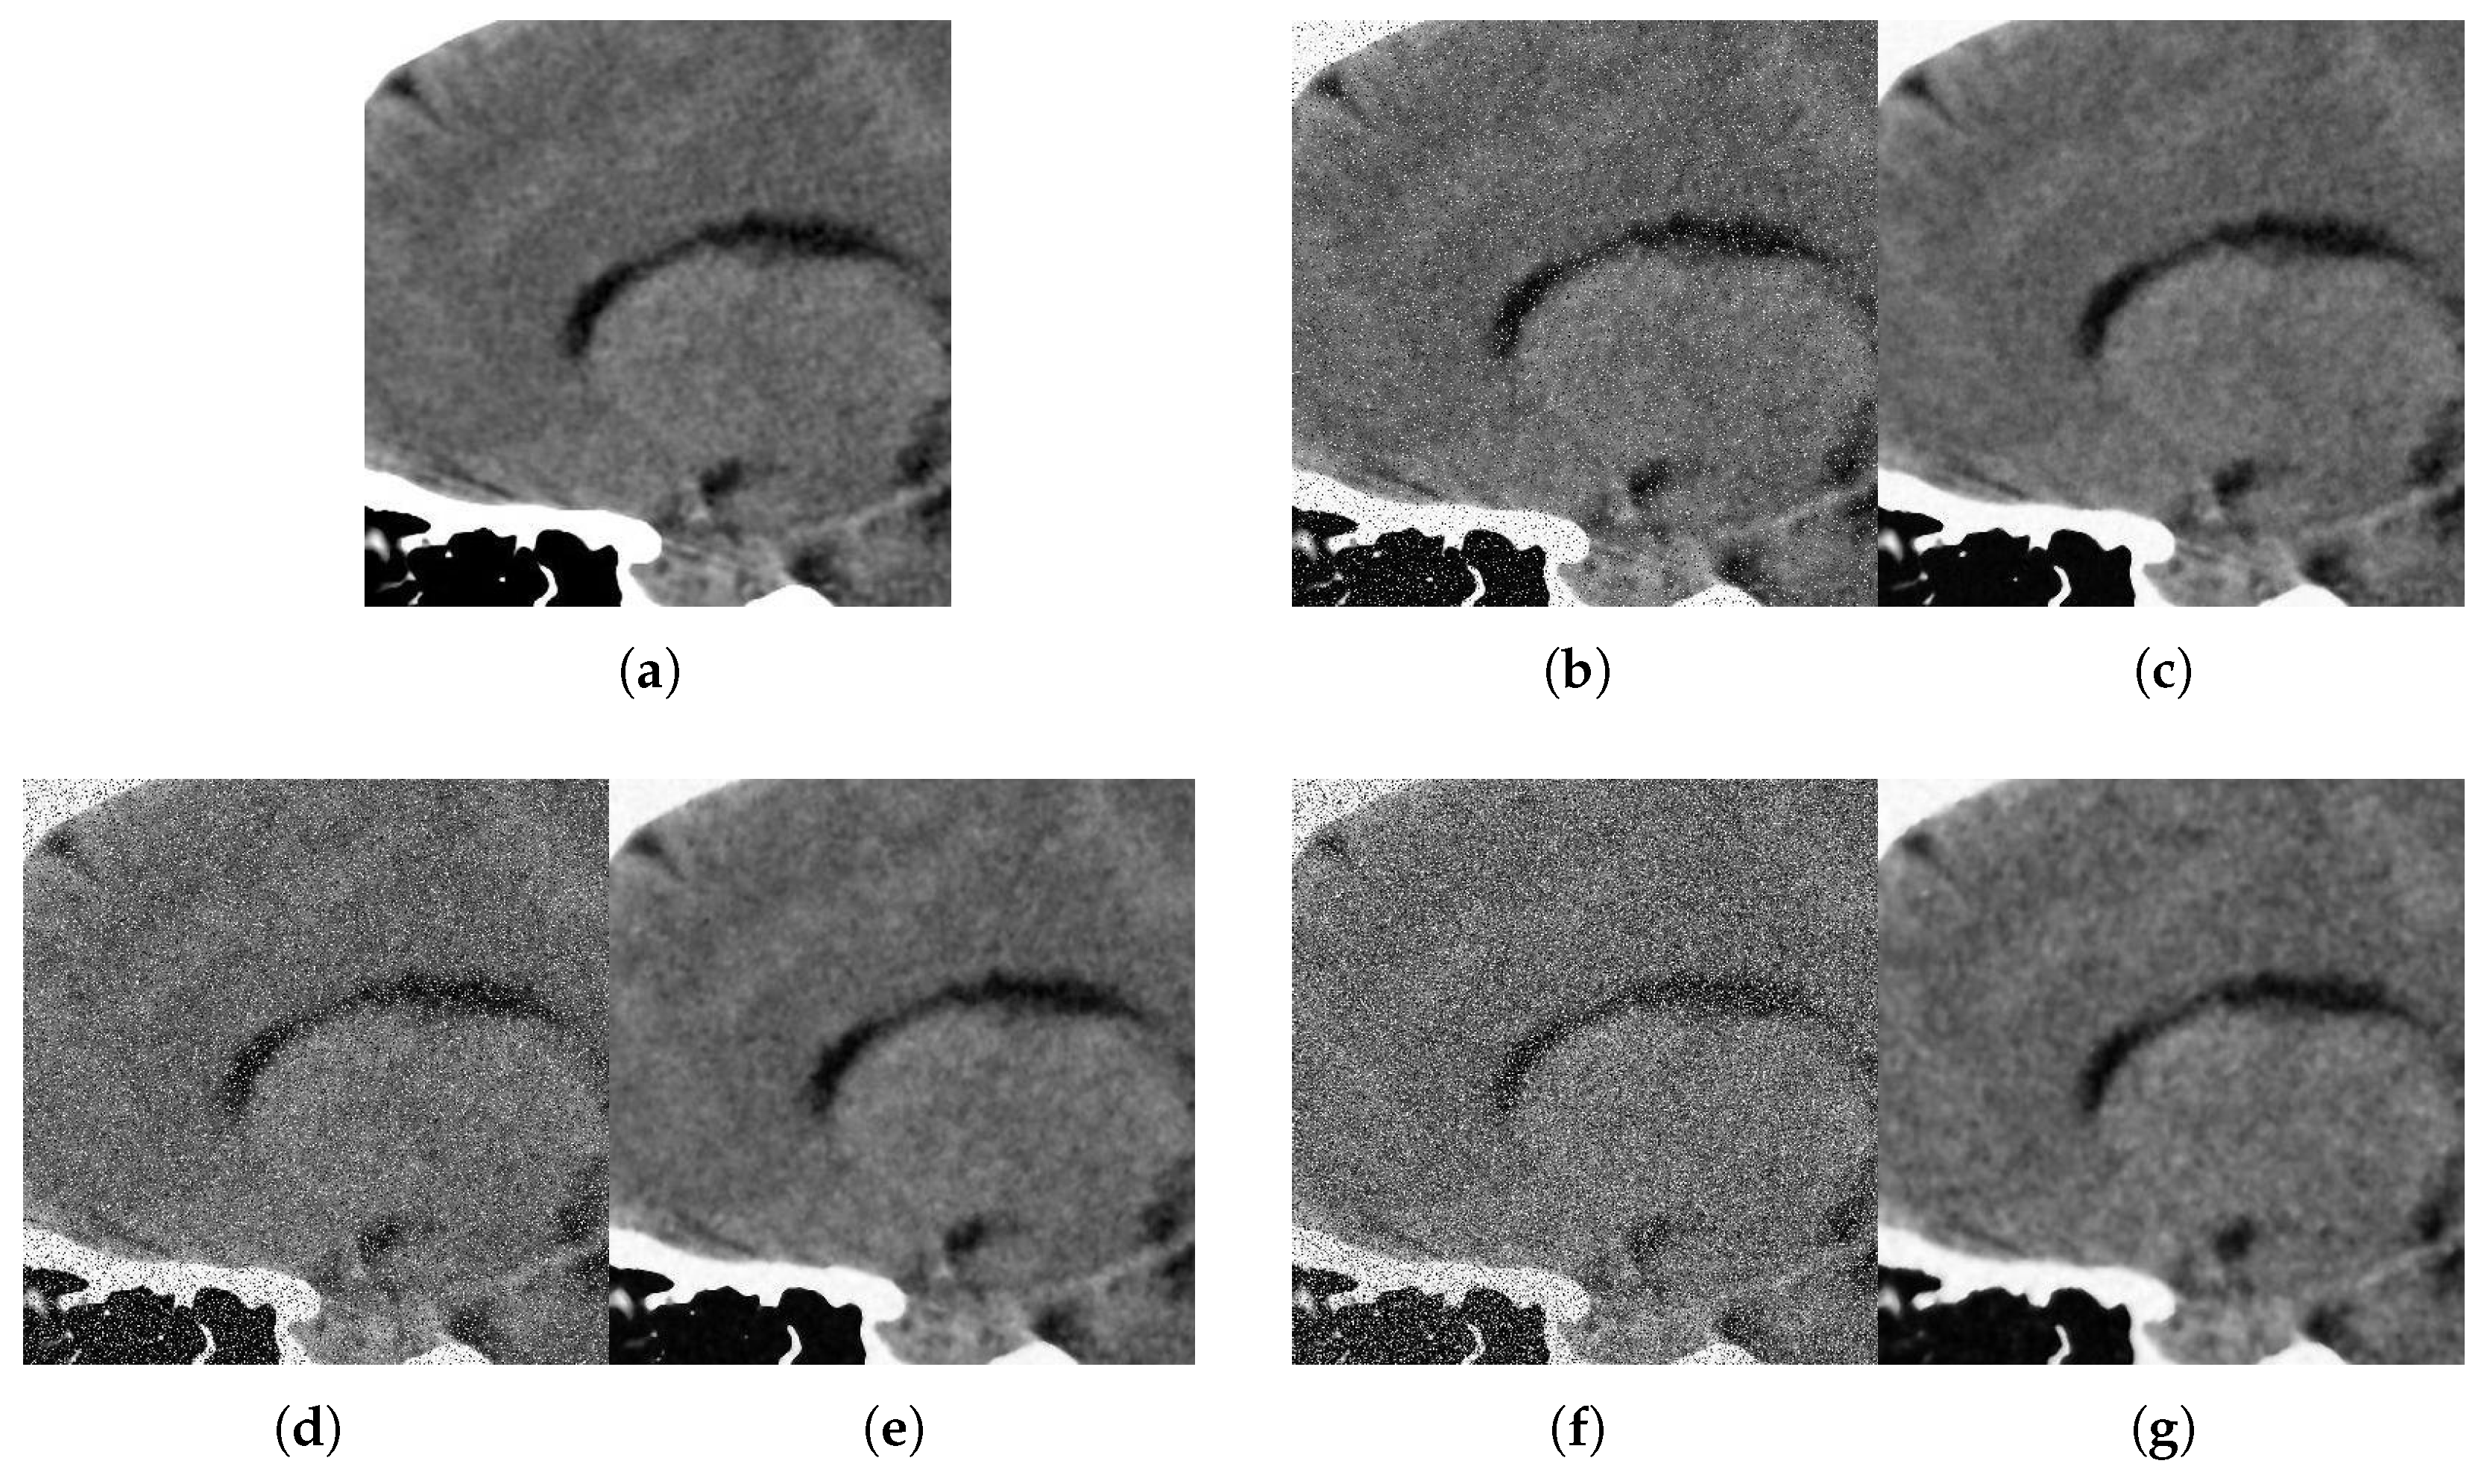

With respect to the visual appearance, by examining the denoised outputs in Figure 10, Figure 11, Figure 12 and Figure 13, we observe that the proposed filter satisfactorily preserves the details of the images and efficiently reduces the Gaussian-impulsive noise.

Figure 10. Method outputs. Axial view corrupted with impulsive noise p and Gaussian σ . (a) Original axial. (b) Noisy p = 0.1 , σ = 10 . (c) Method output. (d) Noisy p = 0.2 , σ = 20 . (e) Method output. (f) Noisy p = 0.3 , σ = 30 . (g) Method output.

Figure 11. Method outputs. Coronal view corrupted with impulsive noise p and Gaussian σ . (a) Original coronal. (b) Noisy p = 0.1 , σ = 10 . (c) Method output. (d) Noisy p = 0.2 , σ = 20 . (e) Method output. (f) Noisy p = 0.3 , σ = 30 . (g) Method output.

Figure 12. Method outputs. Sagittal view corrupted with impulsive noise p and Gaussian σ . (a) Original sagittal. (b) Noisy p = 0.1 , σ = 10 . (c) Method output. (d) Noisy p = 0.2 , σ = 20 . (e) Method output. (f) Noisy p = 0.3 , σ = 30 . (g) Method output.